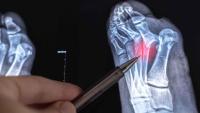

How Are Lisfranc Injuries Diagnosed?

An orthopedic specialist can provide a diagnosis using:

- X-rays to detect fractures or dislocations

- MRI or CT scans are sometimes used to assess ligament damage